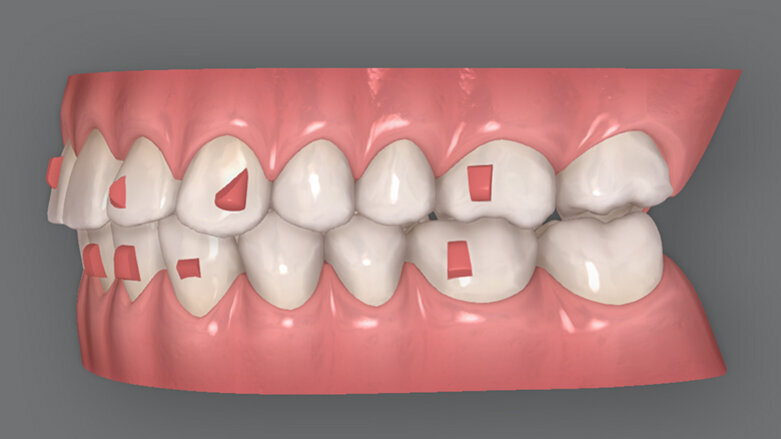

Původní plán léčby ClinCheck sestával ze 14 mandibulárních aktivních alignerů a osmi maxilárních aktivních alignerů, které doplňovaly pasivní fólie. Korunka zubu 33 se má během léčby postupně sklánět lingválně spolu s protruzí dolní fronty, aby se vyřešilo stěsnání řezáků. Pacientka byla instruována, že musí nosit alignery 22 hodin denně, přičemž první a druhý aligner měnila po dvou týdnech a zbylé alignery každý týden.

Byl vygenerován nový ClinCheck, který upravoval tyto problémy. V rámci refinementu bylo vyrobeno 14 nových aktivních alignerů (sedm v každé čelisti). Požádal jsem také technika navíc o tři alignery pro každý oblouk, které stav překompenzovaly, pro dosažení optimálního vyrovnání zubů.